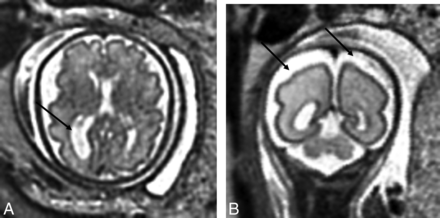

On conventional fetal MR imaging, brain abnormalities were detected in 17 cases (16.3%) and included the following: isolated mild ventriculomegaly (6/17) (Fig 1A), increased extra-axial spaces (4/17) (Fig 1B), white matter cysts (2/17), isolated inferior vermian hypoplasia (2/17), and white matter signal hyperintensity on T2-weighted images (1/17). Of note, one of the fetuses with ventriculomegaly also had a single frontal subependymal cyst. Two fetuses presented with an immature brain appearance based on sulcal-gyral development.

A, T2-weighted axial view of the brain of a 32-week-old fetus with CHD with unilateral ventriculomegaly. B, T2-weighted axial view of the brain of a 27.29-week-old fetus with CHD with extra-axial spaces. Reprinted from Brossard-Racine et al.10